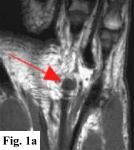

MRI FINDINGS:   MRI was performed on AIC's high-field 1.5 Tesla short-bore Siemens Symphony scanner using a small flexible surface coil. Fig. 1a is a high-resolution coronal DESS, Fig. 1b a sagittal T1 weighted, Fig. 1c a sagittal turbo STIR, and Fig. 1d an axial T1 weighted. They demonstrate a 5x5x7 mm nodule in the volar aspect of the hand at the level of the 4th MCP joint inseparable from the flexor digitorum superficialis tendon (arrows) with some adjacent soft tissue edema. The underlying tendon and bones are otherwise intact.